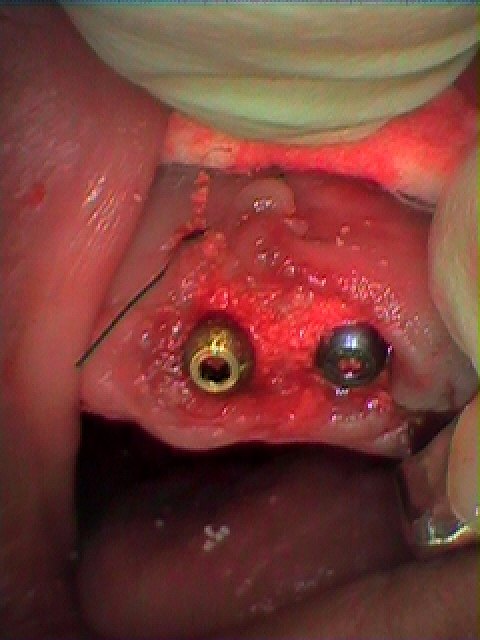

左上2,3番は虫歯も進行しており、抜歯してインプラントとなりました

インプラント埋入時になります

2番部はこのようにインプラントを適正な位置に即時埋入しています